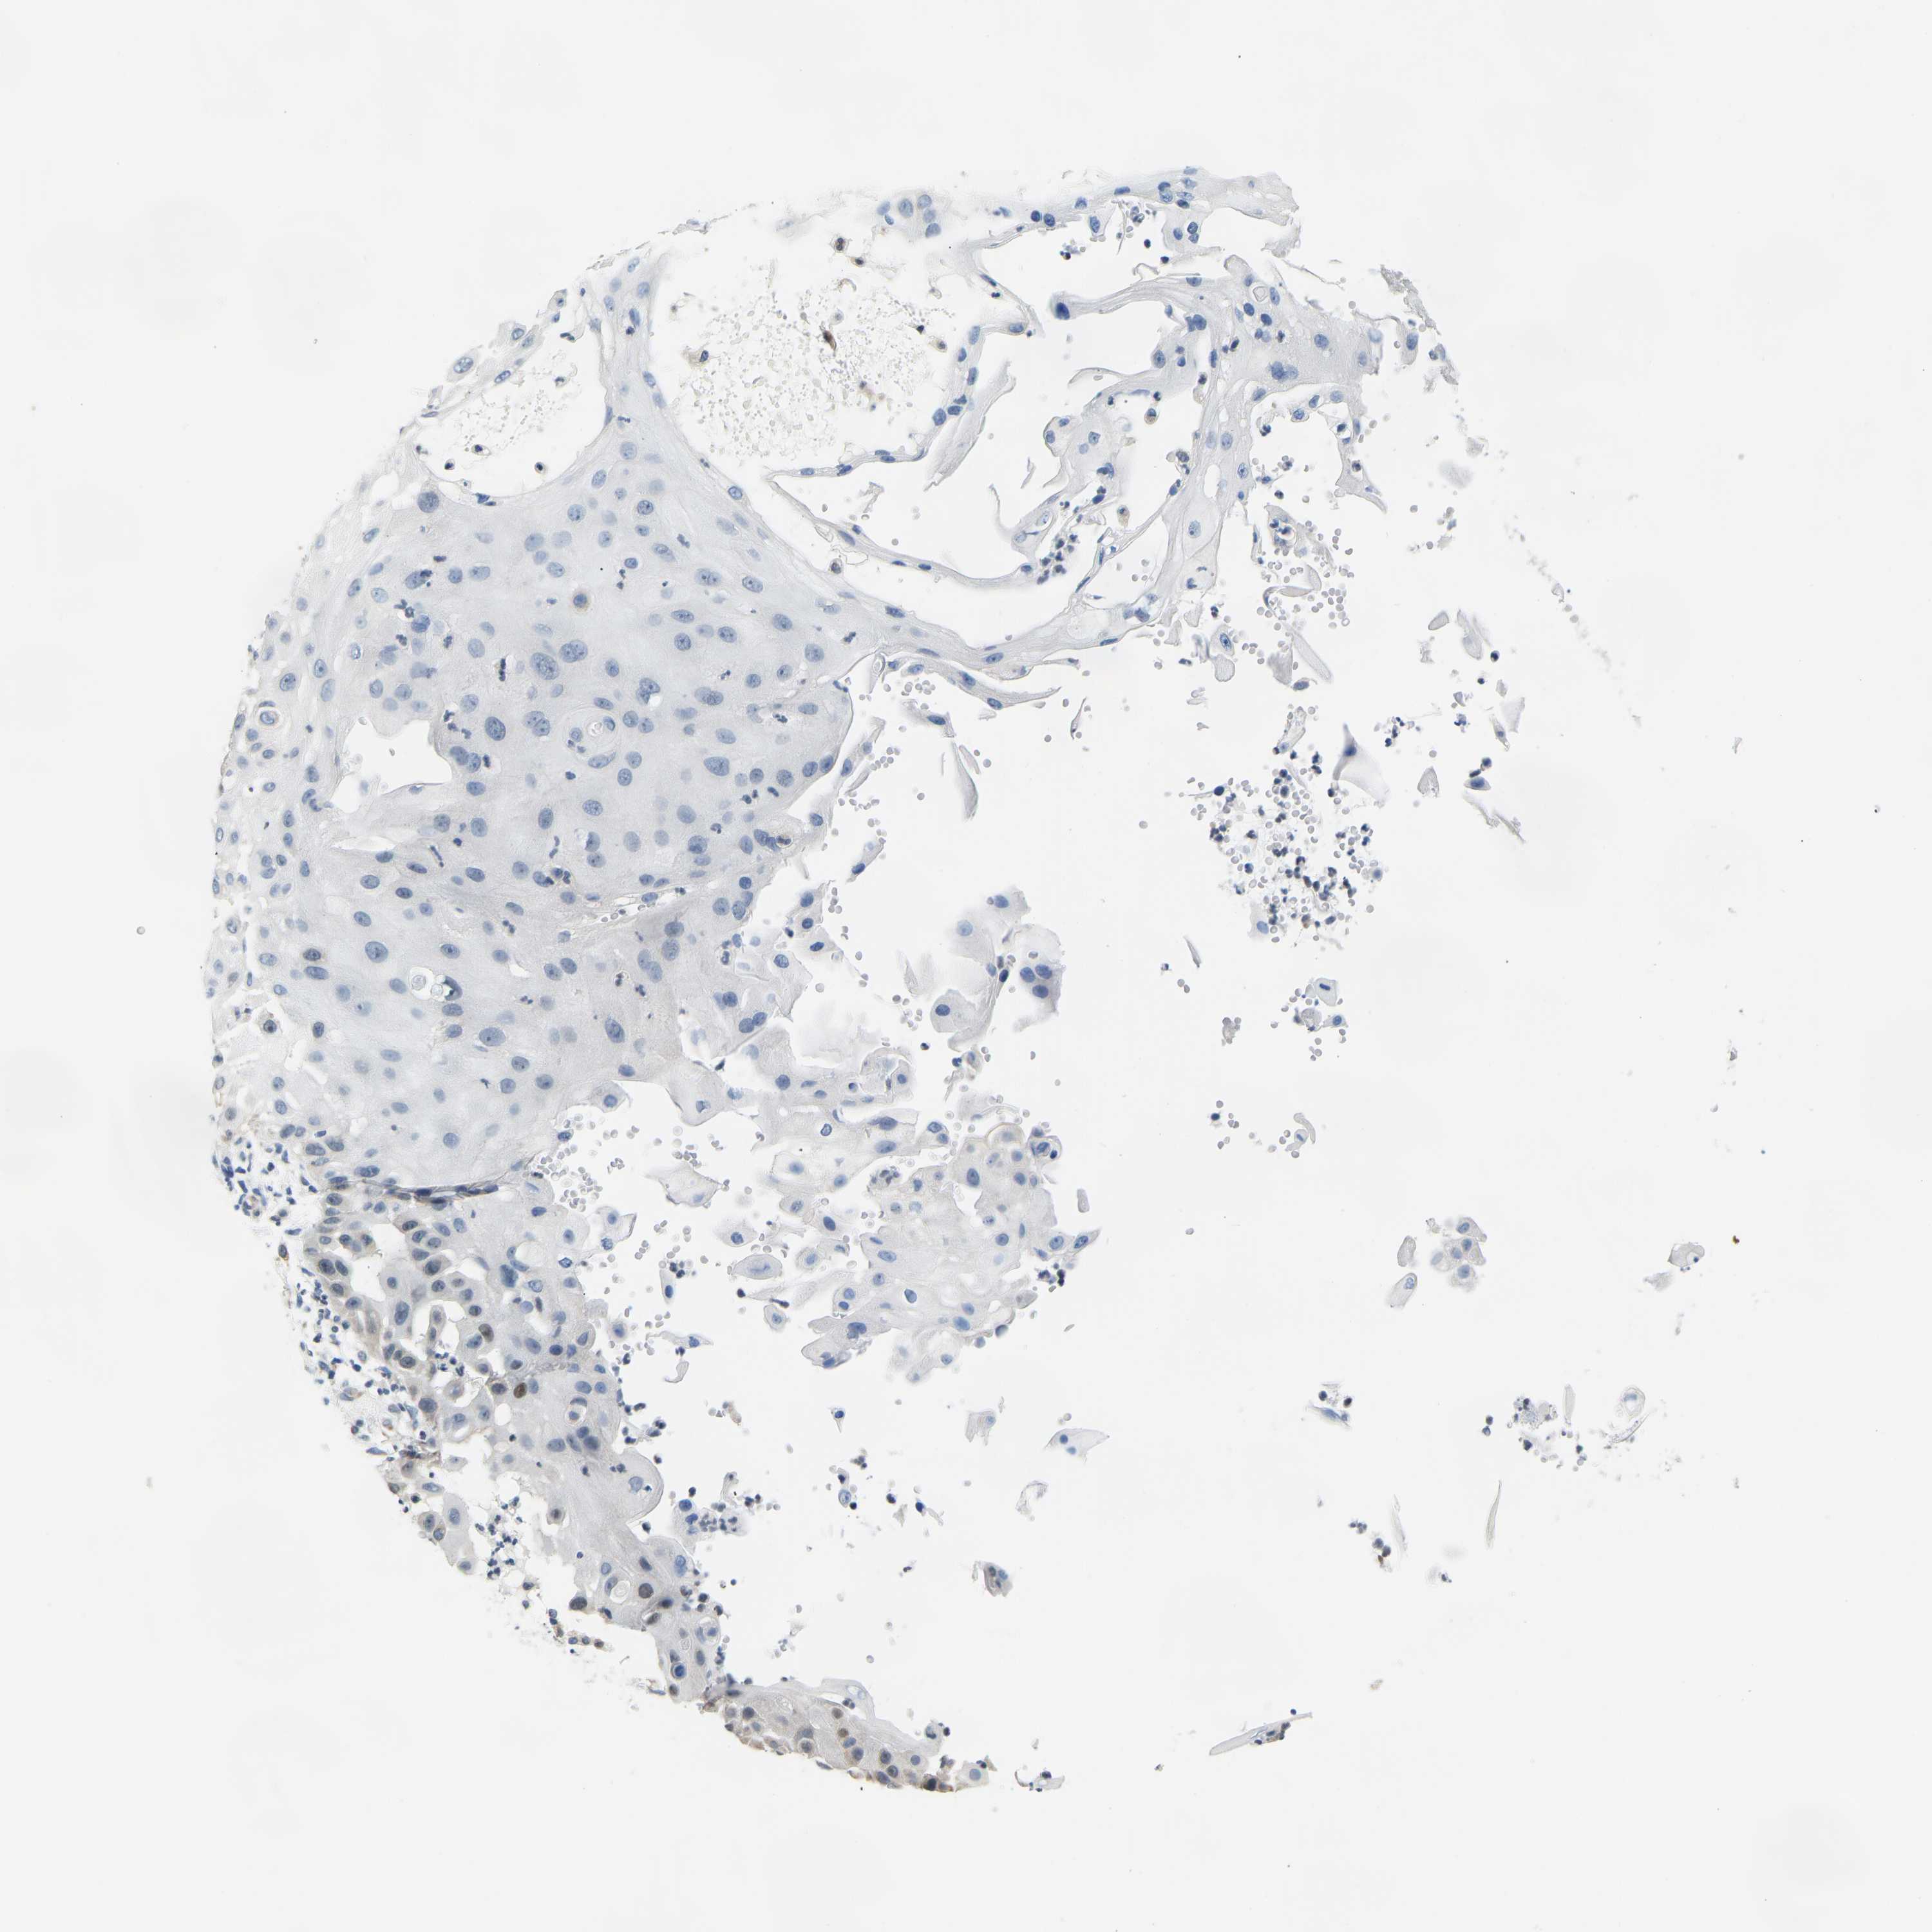

Basal cell and squamous cell cancer

SKIN CANCER - Protein expressioni

A mouse-over function shows sample information and annotation data. Click on an image to view it in a full screen mode. Samples can be filtered based on level of antibody staining by selecting one or several of the following categories: high, medium, low and not detected. The assay and annotation is described here.

Each image is clickable and will lead to virtual microscopy that enables deeper exploration of all samples and also displays staining intensity scores, fraction scores and subcellular localization as well as patient and tissue information for each sample.

Antibody HPA017929

Squamous cell carcinoma, metastatic, NOS